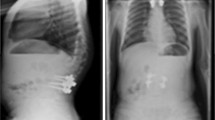

Fourteen patients of this case series finished treatment, so far. Nine received final fusion and five received rod removal without spinal fusion. Within this group the mean Cobb angle was 53.7° (± 7.9) preoperatively and 31° (± 12.9) at final follow-up. The average length of MCGR treatment was 36 months (range: 16–78 months). In those patients who finished treatment the mean T1–T12 height increased 42.5 mm (± 24.3) and the mean T1–S1 height increased 61.1 mm (± 11.6). Due to maximum distraction of the implant one patient received two planned rod exchanges, six patients received one planned rod exchange, and seven patients finished treatment with the first MCGR device. Average time of distraction with one MCGR device was 22.8 months (± 1.1). Figures 4 and 5 show two exemplary cases: one for final fusion (Fig. 4) and one for rod removal without spinal fusion (Fig. 5).

a An 11 year-old girl with a 57° thoracolumbar curve and a 38° thoracic curve. b The same patient after MCGR implantation. c The patient before rod removal, showing the second MCGR in situ. The first MCGR was exchanged after 22 months of distraction (21.45 mm distraction achieved with the right rod and 25.05 mm with the left rod). The second MCGR was in situ for 23 months (22.35 mm distraction achieved with the right rod and 25.09 mm with the left rod) until the left rod broke. d After rod removal the patient has a 22° thoracolumbar and a 23° thoracic curve, and is stable at final follow-up